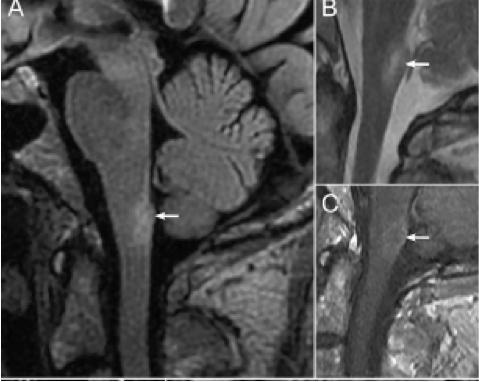

2. NMOSD 视神经MRI:病变较长,累及视交叉